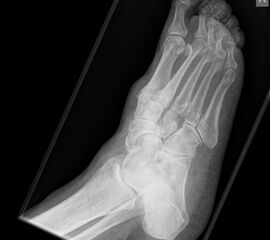

Abbildung 1

Talonavikular-, navikulocuneiforme- und calcaneocuboidale Arthrosen, also Arthrosen in der Chopart- und Bona-Jäger-Gelenklinie, zeigen sich wesentlich seltener und können in Kombination von Arthrosen aller Gelenke des Mittelfußes auftreten. Die Diagnostik beinhaltet grundsätzlich die ausführliche Untersuchung des gesamten Fußes im Stehen, im Liegen und beim Gehen. Ein Röntgenbild des Fußes im Stehen in zwei Ebenen, ergänzend eine schräge Aufnahme, sowie Saltzman und OSG-Bildgebung sind für die Diagnose und Therapieplanung essentiell. Bei Planung eines operativen Eingriffes sollte eine Computertomographie des gesamten Fußes durchgeführt werden. Zunächst sollte die konservative Therapie mittels Schmerzmedikation, Infiltration, Manueller Therapie, Einlagen, Schuh-Modifikation, Orthesen, orthopädischem Schuhwerk und ggf. eine Strahlentherapie voll ausgeschöpft werden. In zweiter Linie steht die operative Therapie. Chirurgische Eingriffe beinhalten typischer Weise die selektiven Arthrodesen der betroffenen Mittelfußgelenke. Hier wird meist die mediale Säule behandelt, die Arthrodesen der mobileren lateralen Säule sind ein Thema in der Diskussion 2.

Die Diagnostik beinhaltet die komplette klinische Untersuchung des Patienten bei entkleidetem Unterkörper mit Funktionstests, Abtasten der entsprechenden Gelenkreihen (Chopart, Bona Jäger und Lisfranc) und Überprüfung der Beweglichkeit der Tarsometatarsalgelenke mit dem Klaviertasten-Test 11. Beurteilt werden Fußformveränderungen, osteophytäre Anbauten, sowie eine mögliche Verkürzung des M. gastrocnemius-soleus-Komplexes mit Hilfe des Silfverskjöld-Tests 12. Es werdemRöntgenaufnahmen des Fußes im Stehen in 2 Ebenen und ergänzend eine Schrägaufnahme des Fußes durchgeführt. Bei Fußfehlstellungen erfolgt zusätzlich das Röntgen des oberen Sprunggelenks im Stehen und eine Saltzman-Aufnahme 13.